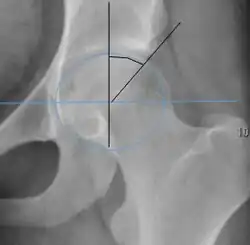

Measurements of impingement on X-ray.[notes 1][20]

Alpha angle

Measured in 45° Dunn view.

Degree of bulging of the femoral head-neck junction: In normal conditions there is a symmetric concave contour at the junction of the femoral head and neck. Loss of this concavity or bone bulging may lead to cam type impingement. The degree of this deformity can be measured by the alpha angle. Although it can be measured in the cross-lateral view, the 45° Dunn view is considered more sensitive and the frog leg view more specific in determining pathologic values.

• Normal: ≤68° in men, ≤50° in women

• Borderline: 69° to 82° in men, 51° to 56° in women

• Pathological: ≥83° in men and ≥57° in women